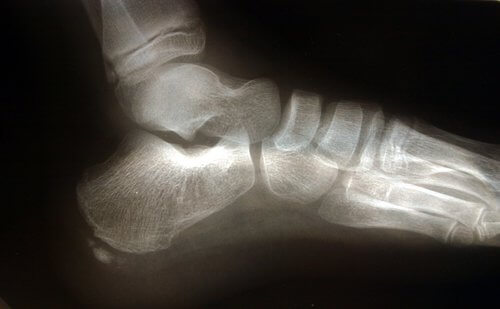

Anatomia del piede

Sono diverse le strutture anatomiche che permettono la flessione plantare e che possono, quindi, provocare il sovraccarico della fascia plantare.

Il tendine d’Achille è un legamento che va dal muscolo gastrocnemio (o muscoli gemelli) e dal soleo fino al calcagno. La contrazione del tendine di Achille provoca un aumento di pressione sul calcagno e, successivamente, un aumento di pressione sul legamento arcuato.

Un altro fattore anatomico da considerare è l’appoggio del piede, ossia il modo in cui il piede poggia a terra. I piedi piatti o la tendenza pronatoria provocano un maggiore stiramento della fascia plantare aumentando il rischio di lacerazione del tessuto a causa della maggiore pressione esercitata.

Spesso la presenza di fascite plantare si verifica in concomitanza con lo sviluppo della spina calcaneare, sebbene non ne sia un sintomo determinante.